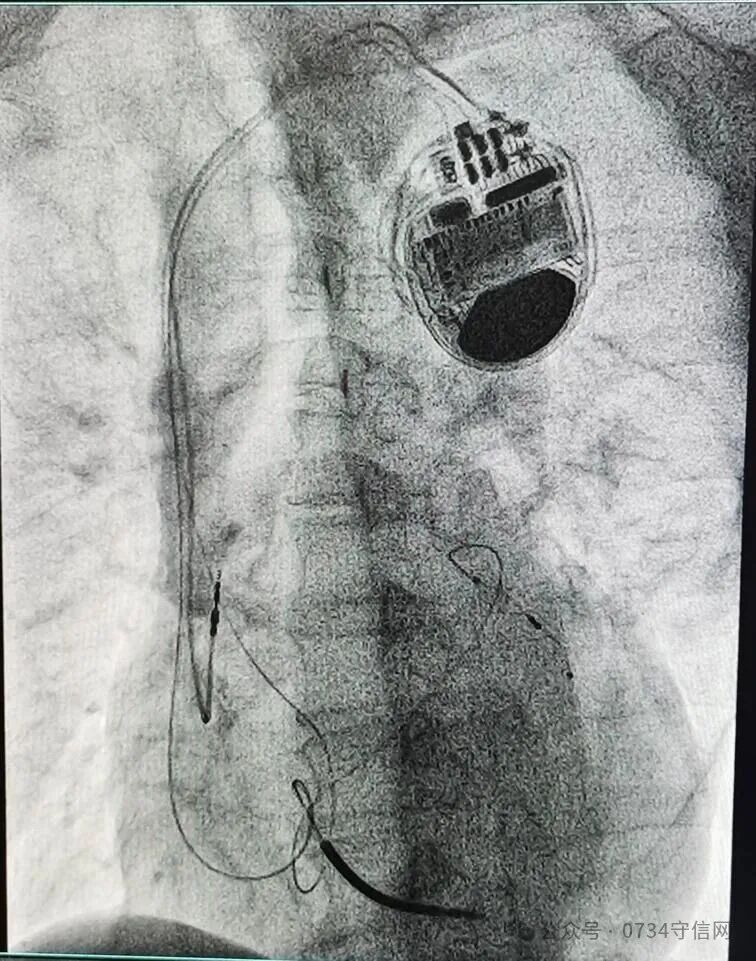

——衡阳市第一人民医院成功开展衡阳地区首例3.0T MRI兼容CRTD植入术

近日,衡阳市第一人民医院心血管内科专家团队成功为一名终末期心力衰竭患者,实施了衡阳地区首例3.0T磁共振(MRI)兼容心脏再同步化治疗心律转复除颤器(CRT-D)植入术。此项技术的开展,填补了区域内该领域的技术空白,标志着该院心脏起搏与电生理诊疗技术实现了跨越式提升,为当地心衰患者带来了新的生命守护方案。

作为心力衰竭治疗的“终极武器”之一,CRT-D(俗称“三腔除颤器”)是集治疗与防护于一体的高端医疗设备。它既具备心脏再同步治疗(CRT)的核心作用,又拥有植入式心律转复除颤器(ICD)的急救功能,为患者的生命安全拴上“双保险”。此次手术的关键突破在于“3.0T MRI兼容”。传统CRTD设备因受电磁兼容性限制,患者术后无法接受高磁场强MRI检查,而MRI作为多种疾病(如肿瘤、脑血管疾病)的重要诊查手段,其检查限制往往给患者后续诊疗带来极大困扰。3.0T MRI兼容型CRTD的成功应用,彻底打破了这一壁垒,患者术后可自由接受3.0T MRI检查,既不影响设备正常工作,又能获得全面精准的后续诊断,极大提升了治疗的安全性与便利性。